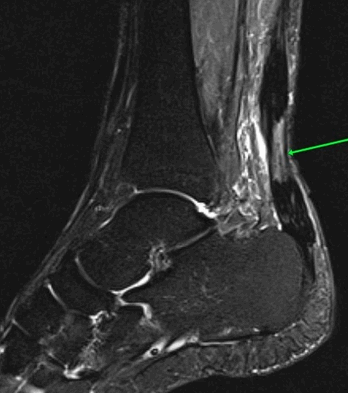

Рис4. а. на КТ перелом таранной и большеберцовой костей, б. на МРТ перелом таранной кости